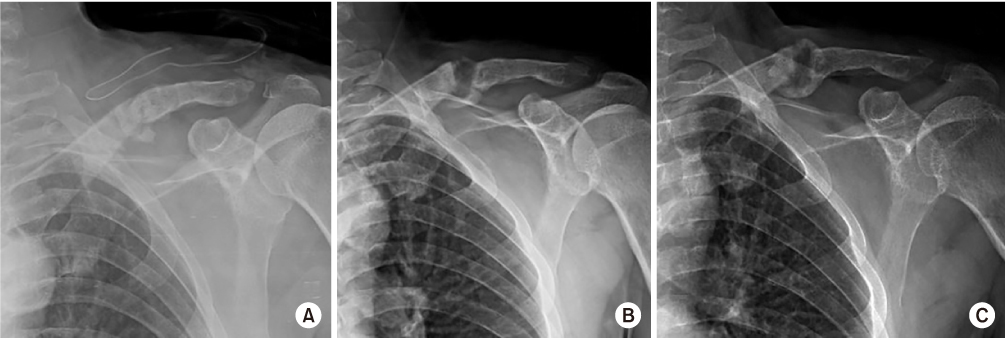

A 56-year-old, right-hand-dominant, male patient was transferred to our hospital for nonunion of mid-shaft clavicular fracture. The patient's first operation was performed at another hospital 5 months prior, where a plate and screws were implanted for repair (Fig. 1). His radiographs upon admission revealed loosening of the implant. On physical examination, he presented with left shoulder discomfort, tenderness along his fracture site of the left clavicle, and limited range of motion of the left shoulder secondary to pain. Neurovascular status was intact. When compared to radiographs obtained after the first operation, radiographs of the clavicle taken at admission demonstrated increased angulation of the fracture site with a visible fracture site gap and distal implant loosening (Fig. 1). He also had avascular necrosis of bilateral femoral heads. We performed a revisionary open reduction and internal fixation of the left clavicle with an autogenous cancellous bone graft from left femoral head after simultaneous left total hip arthroplasty. We recommended right total hip arthroplasty.

The surgery of the clavicle was performed by a shoulder specialist at our hospital. An incision was made along the clavicular axis on the previous operation scar. The previous plate and screws leaving out a lag screw were removed. Fibrous and granulated tissue of the nonunion site was excised and the ends of each fragment were prepared with curettage. Fracture reduction and fixation were achieved with a longer locking compression plate. The autogenous cancellous bone graft from the left femoral head was packed in the fracture gap after total hip arthroplasty. The wound was closed in a layered fashion after confirmation of satisfactory fracture reduction and implant position with an image intensifier (Fig. 2).

Immediate postoperative left clavicle anteroposterior view after the first surgery.